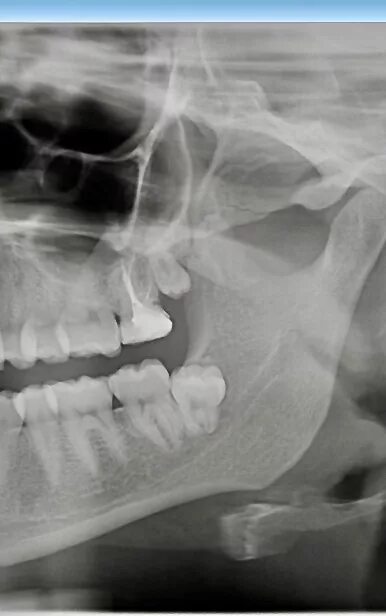

Удалить зуб митино